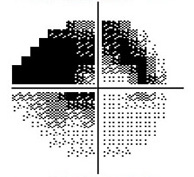

Normal Visual Field

Moderate Visual Field Loss

Severe Visual Field Loss